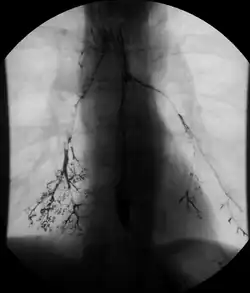

- Aspiration or inhalation of barium sulfate into the lungs during oral application can lead to serious respiratory complications leading to fatal aspiration pneumonia or asphyxiation.[35]